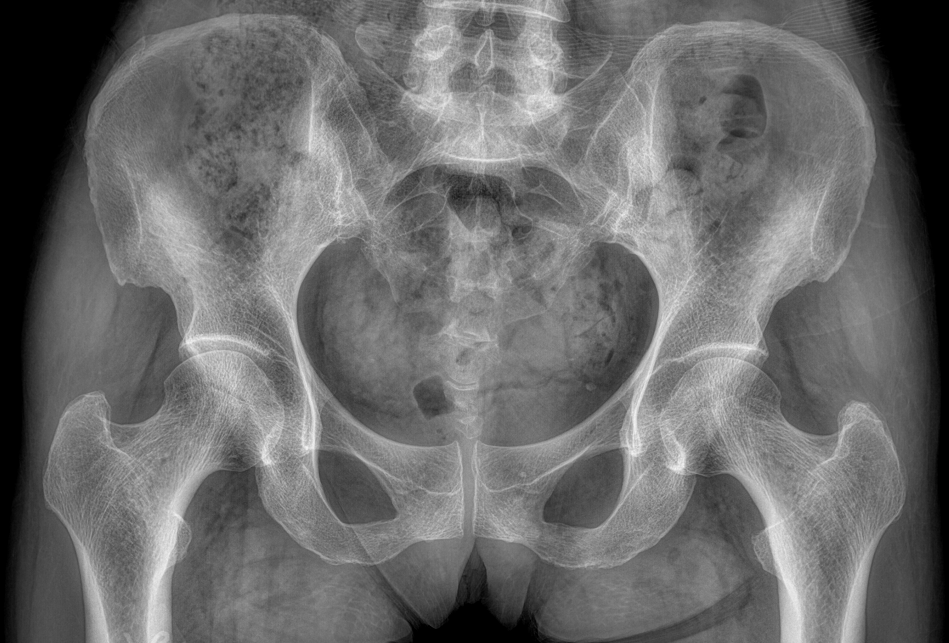

临床图像